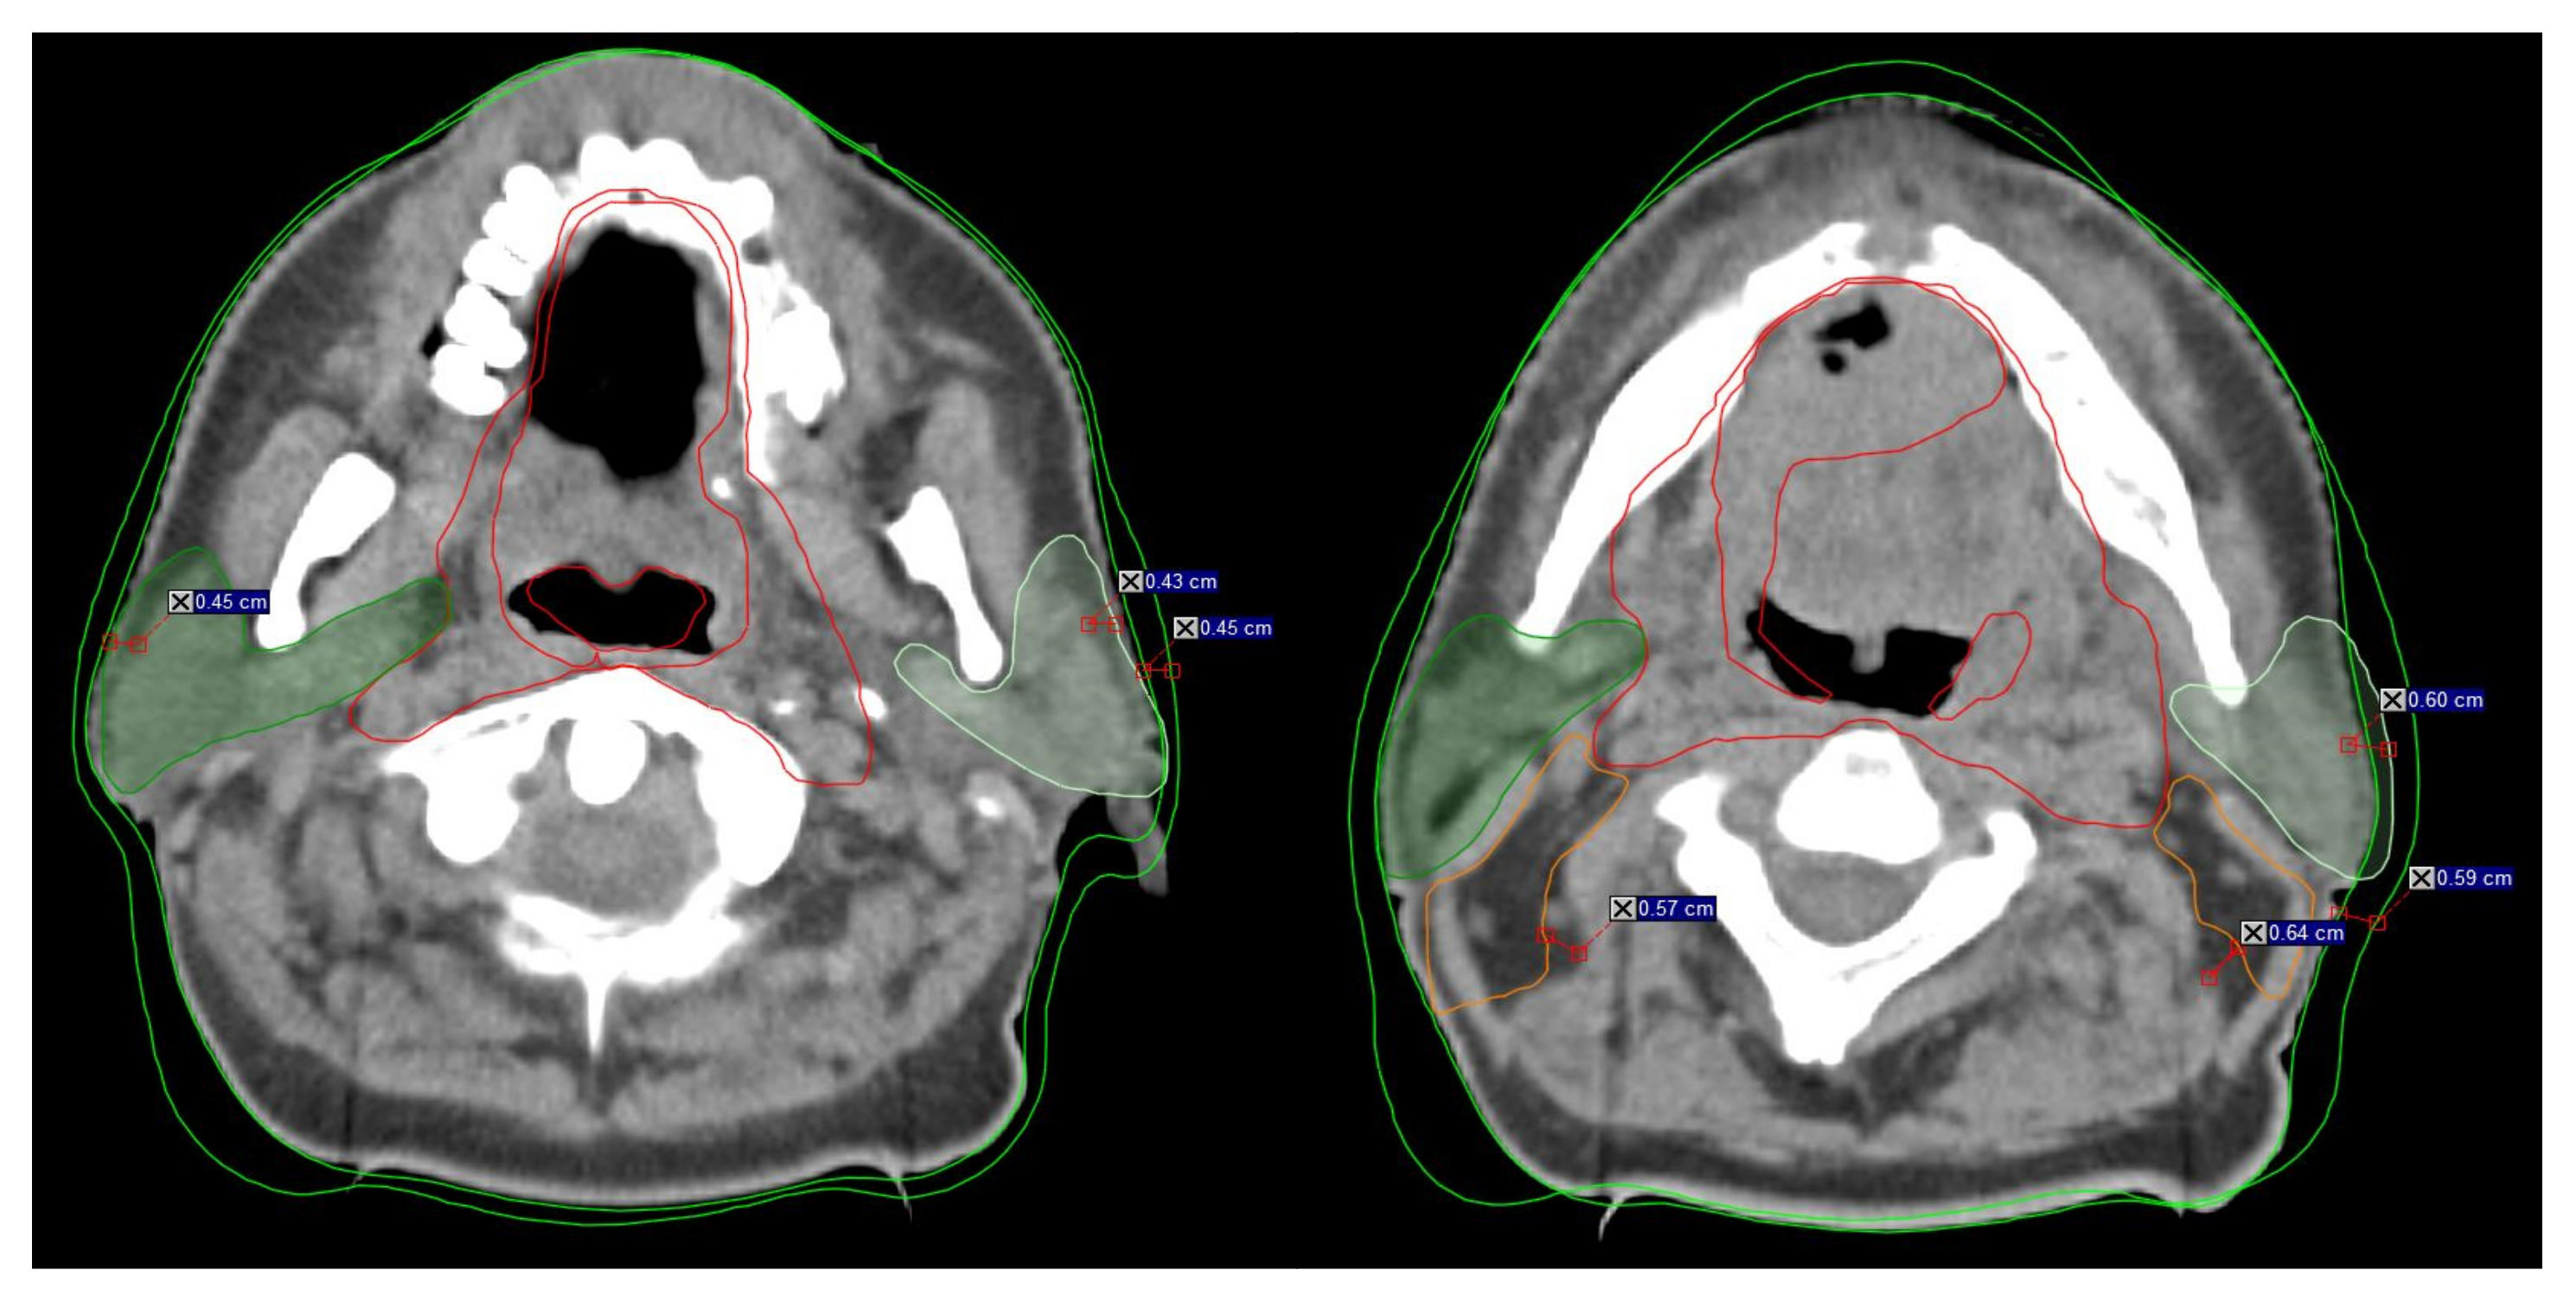

| Structure | Alert | Assessment | Criteria |

|---|---|---|---|

| Parotid Glands | The difference between the iCT and the CBCT/MVCT at any point of the external contour | Superficial part of PG (the area near masseter muscle) | >3 mm on 3–4 consecutive scans |

| PG shrinkage | Deep part of the PG lobe | ||

| PG shift medially in the high-risk region | Medial pterygoid muscle | ||

| CTV 1 (Tumor) | The difference between the iCT and the CBCT/MVCT in any direction | CTV1 contour and position changes | >3 mm on 3–4 consecutive scans |

| CTV1 overlaps OARs (muscles, PG, bones, air cavities) | |||

| CTV 2 (Nodal region) | The difference between the iCT and the CBCT/MVCT, especially in the nodal levels II–IV | CTV2 contour and position changes | >3 mm on 3–4 consecutive scans |

| CTV2 overlaps OARs (muscles, PG, bones, air cavities) | |||

| PTV | The difference between the iCT and the CBCT/MVCT at any point of the external contour (PTV outside the body) | PTV contour and position changes | >3 mm on 3–4 consecutive scans |

| Body contour/weight changes |